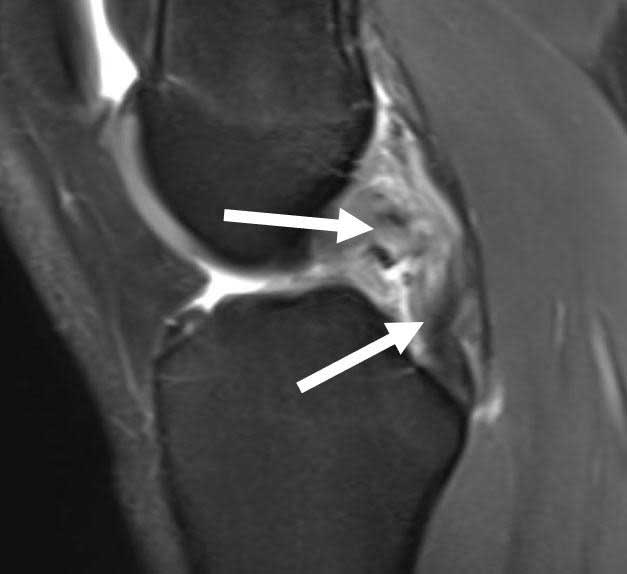

From radiologi.id

ACL and PCL tear MRI radiologi.id Yoga For Pcl Tear Expert online yoga classes for knee injuries recovery and improve flexibility &. yoga for acl & pcl injuries: There are a number of yoga asanas that can aid in the rehabilitation process of partially torn. yoga for rehabilitation. have you ever considered the power of yoga in healing? in today’s digital age, recovering from an acl. Yoga For Pcl Tear.